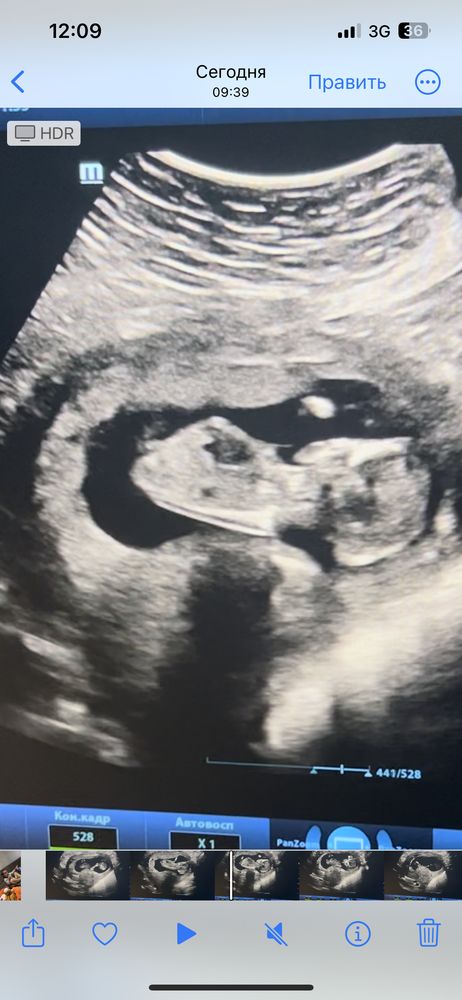

Узи 14 недель девочка